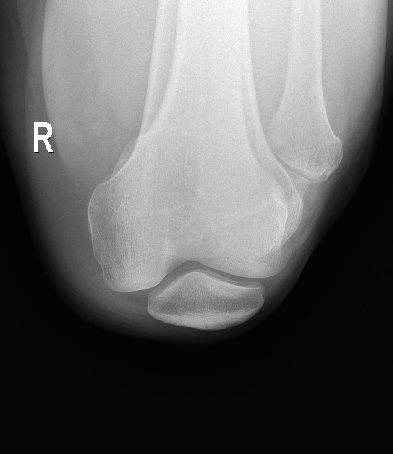

ЧрБъїК±ИЛЙъѕНКЗІ©їЖјјЧФЦчСР·ўµД¶ЇМ¬МЅІвЖчјјКхЈ¬ИГБЩґІјмІйѕЯ±ёїЙКУ»ЇМхјюЈ¬ІўКµПЦїмЛЩёЯЗеµгЖ¬Ј¬

ѕ«ЧјІ¶ЧЅІЎФоЎЈКµПЦґУ¶юО¬ЅвЖКіЙПсµЅЖч№Щ№¦ДЬіЙПсЧЄ±дЈ¬ИГХп¶Пёьѕ«ЧјЎЈ

ёЯЗе¶ЇМ¬

ЖЅ°еМЅІвЖч

З§Нтј¶ПсЛШОЮПЯЖЅ°еМЅІвЖчЈ¬ЦЗДЬФЪПЯідµз -

ёЯЦКБїУ°ПсјґК±ґ¦АнЈ¬¶ЇМ¬У°ПсїЙѕЦІї·ЕґуЈ¬»Ш·ЕК±їЙИОТв¶ОЅШИЎЈ¬±ЈґжІў PACSґ«КдЎЈ